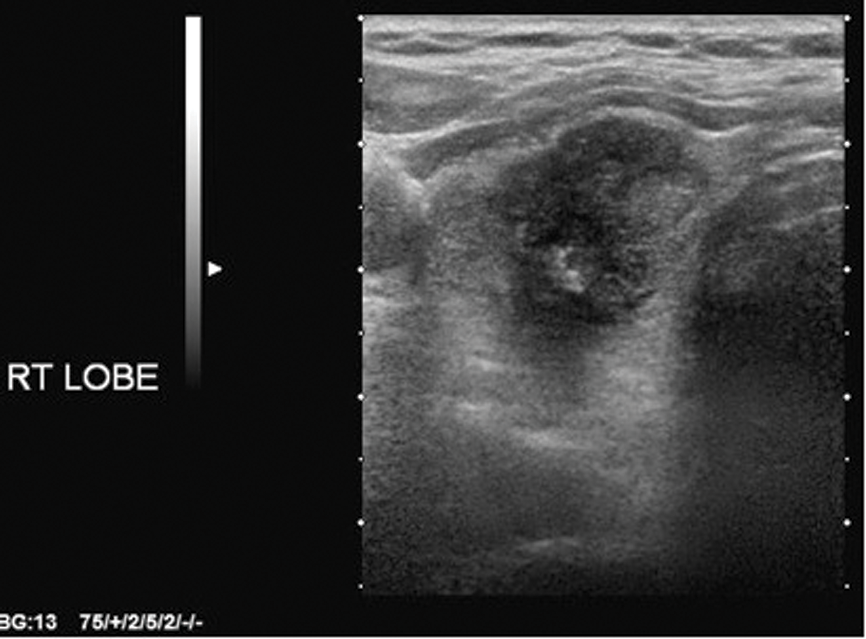

There are a few important points to consider: it is papillary cancer that is accounting for the increase in thyroid cancer incidence, and the four US features used in the Kim and AACE criteria are the cardinal features of papillary cancer (Figures 1-4). For high sensitivity, the Kim Criteria should be used, for high specificity, AACE criteria. The use of nodule size reduces sensitivity and specificity quite markedly.

Figure 1: Solid, hypoechoic right lobe of thyroid mass.